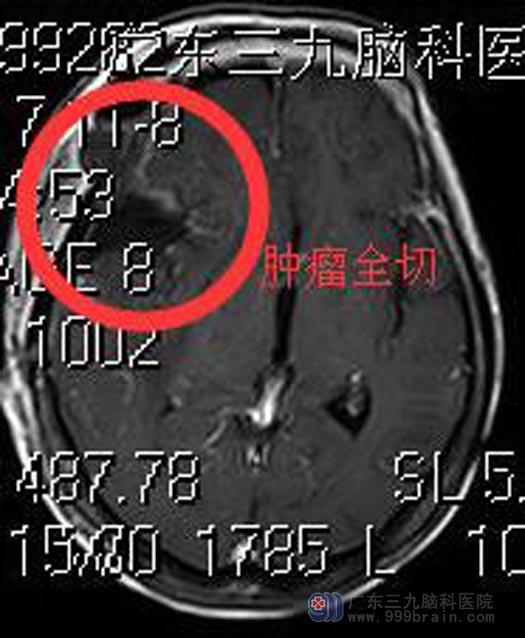

在全麻下行全脑血管造影+肿瘤介入栓塞术,术中栓塞部分供血血管,术毕送入手术室。由鲁明主任主刀,在全麻下行右侧蝶骨嵴脑膜瘤切除术,术中显微镜下见灰白色肿瘤部分裸露,肿瘤质软,有完整包膜,血供栓塞后出血量较少,仔细分离出颈内动脉、大脑中动脉、大脑前动脉及视神经,完整切除肿瘤,颈内动脉、大脑中动脉、大脑前动脉、视神经、动眼神经保护完整,手术过程顺利。术后刘阿姨神志清醒。术后病理结果:脑膜瘤。

手术后